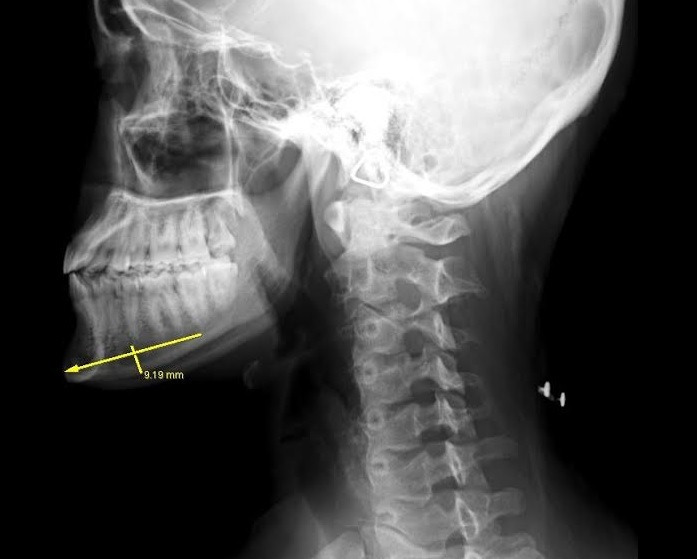

20代女性、顎が長いこと、

しゃくれていることを気にされ

顎骨切りの適応にて手術を行いました。

正面視では下口唇からオトガイ先端までの距離が長く、

フェイスラインも比較的細いため、

中央を大きめに切除し、

やや発達気味の左側を大きめで切除します。

下顎の前突(しゃくれ)については骨きりの際、

大部分が切除でき、残りはサージカルモーターで

削ることにしました。

切除できた骨片は、

横幅6.3cm 最大厚 左9mm 右8mm 中央6mmで

今回もほぼデザインどおりの切除が行えました。